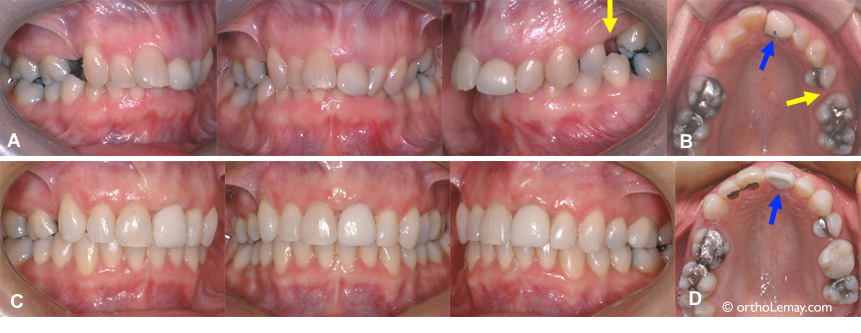

• (A) Adulte de 24 ans ayant des arcades étroites, du chevauchement dentaire sévère (manque d’espace) et une latérale en linguo-version (du côté du palais). Les premières molaires étant sévèrement endommagées, il fut décidé de les extraire (*) pour éviter la nécessité de faire des couronnes prothétiques et possiblement des traitements de canal plus tard.

• (B) 10 semaines plus tard,  l’expansion progresse bien mais la majeure partie de l’espace où les molaires ont été extraites reste à fermer.

• (C) 10.5 mois lus tard (soit 12 mois au total), l’expansion est obtenue et les espaces d’extraction sont fermés complètement. La latérale droite qui était du côté du palais est maintenant alignée dans l’arcade dentaire.

• Le traitement n’est pas terminé mais les arcades ont des proportions harmonieuses et le chevauchement est éliminé.